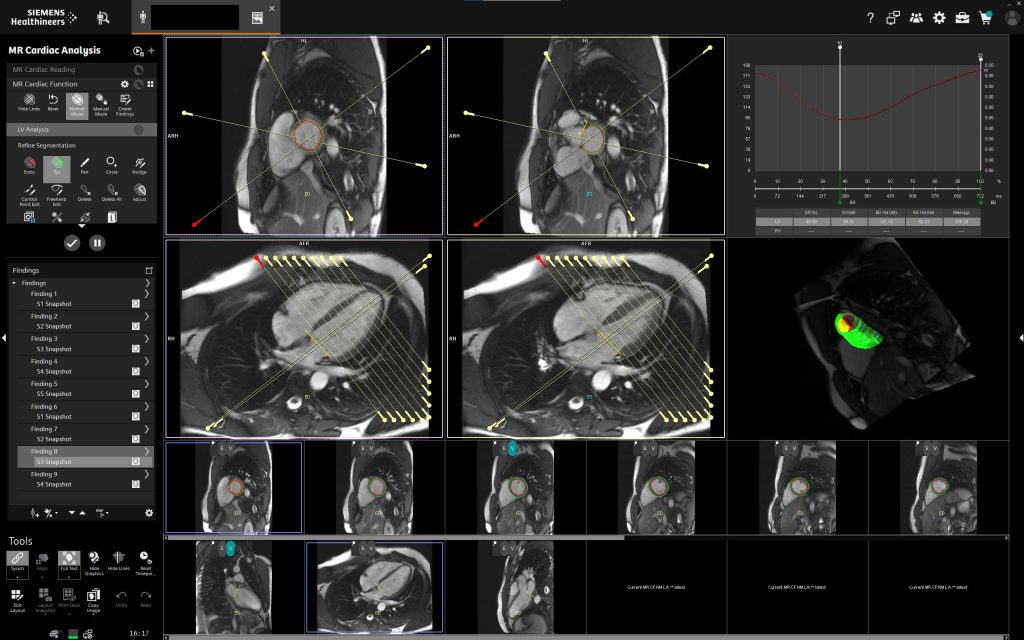

У клініці «Церебрум» МРТ серця представляє собою передовий неінвазивний метод, що дозволяє отримати надзвичайно точні дані про анатомію та функціональний стан серця.

Використання потужного магніту Siemens QS (45/200) із 16 канальною спеціалізованою серцевою котушкою та подальшою постобробкою на робочій станції Siemens Via забезпечує найвищий рівень діагностичної точності, недосяжний для традиційних методів дослідження.

- Високоточна анатомічна деталізація — метод дозволяє виявляти мінімальні структурні зміни міокарда, клапанів та коронарних судин, що забезпечує раннє виявлення патологій ще до появи клінічних симптомів.

- Комплексна функціональна оцінка — одночасний аналіз руху стінок серця, скоротливості шлуночків, роботи клапанів і кровотоку забезпечує всебічну оцінку роботи серцево-судинної системи.

- Сучасні технології обробки зображень та оперативне отримання результатів — високоякісні 3D-знімки та швидке формування детального висновку забезпечують прийняття точних клінічних рішень у найкоротші терміни.